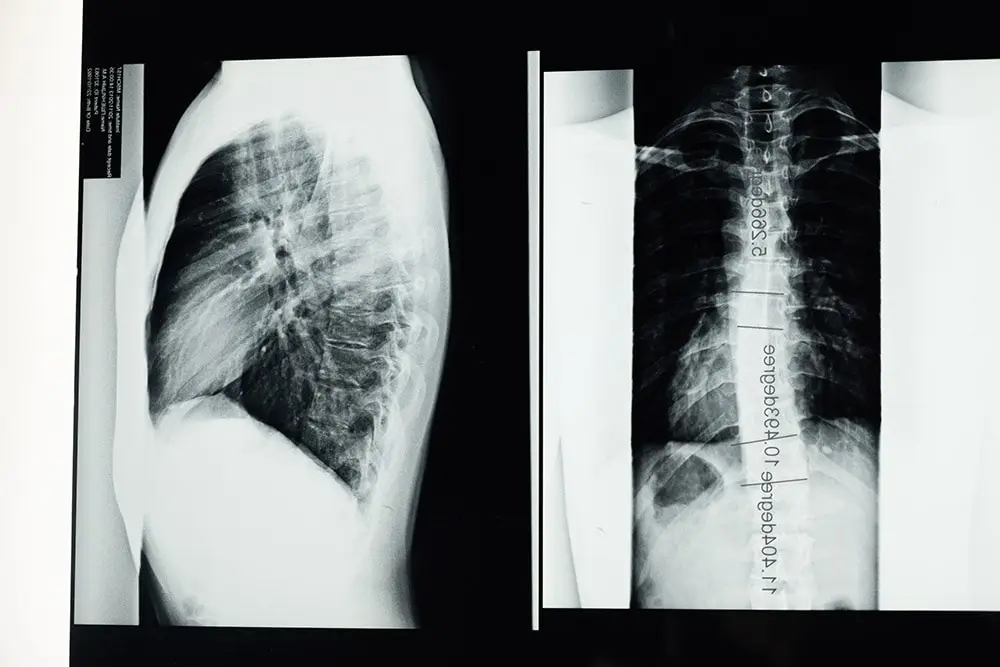

Pierwszym krokiem do rozpoznania jest badanie wizualne. Lekarz może również zlecić badania obrazowe kręgosłupa. Może również poprosić Cię o wykonanie prostych ćwiczeń w celu sprawdzenia ułożenia poszczególnych odcinków kręgosłupa.

Badania obrazowe kręgosłupa obejmują rentgen, skan MRI, skan CT, skan kości.